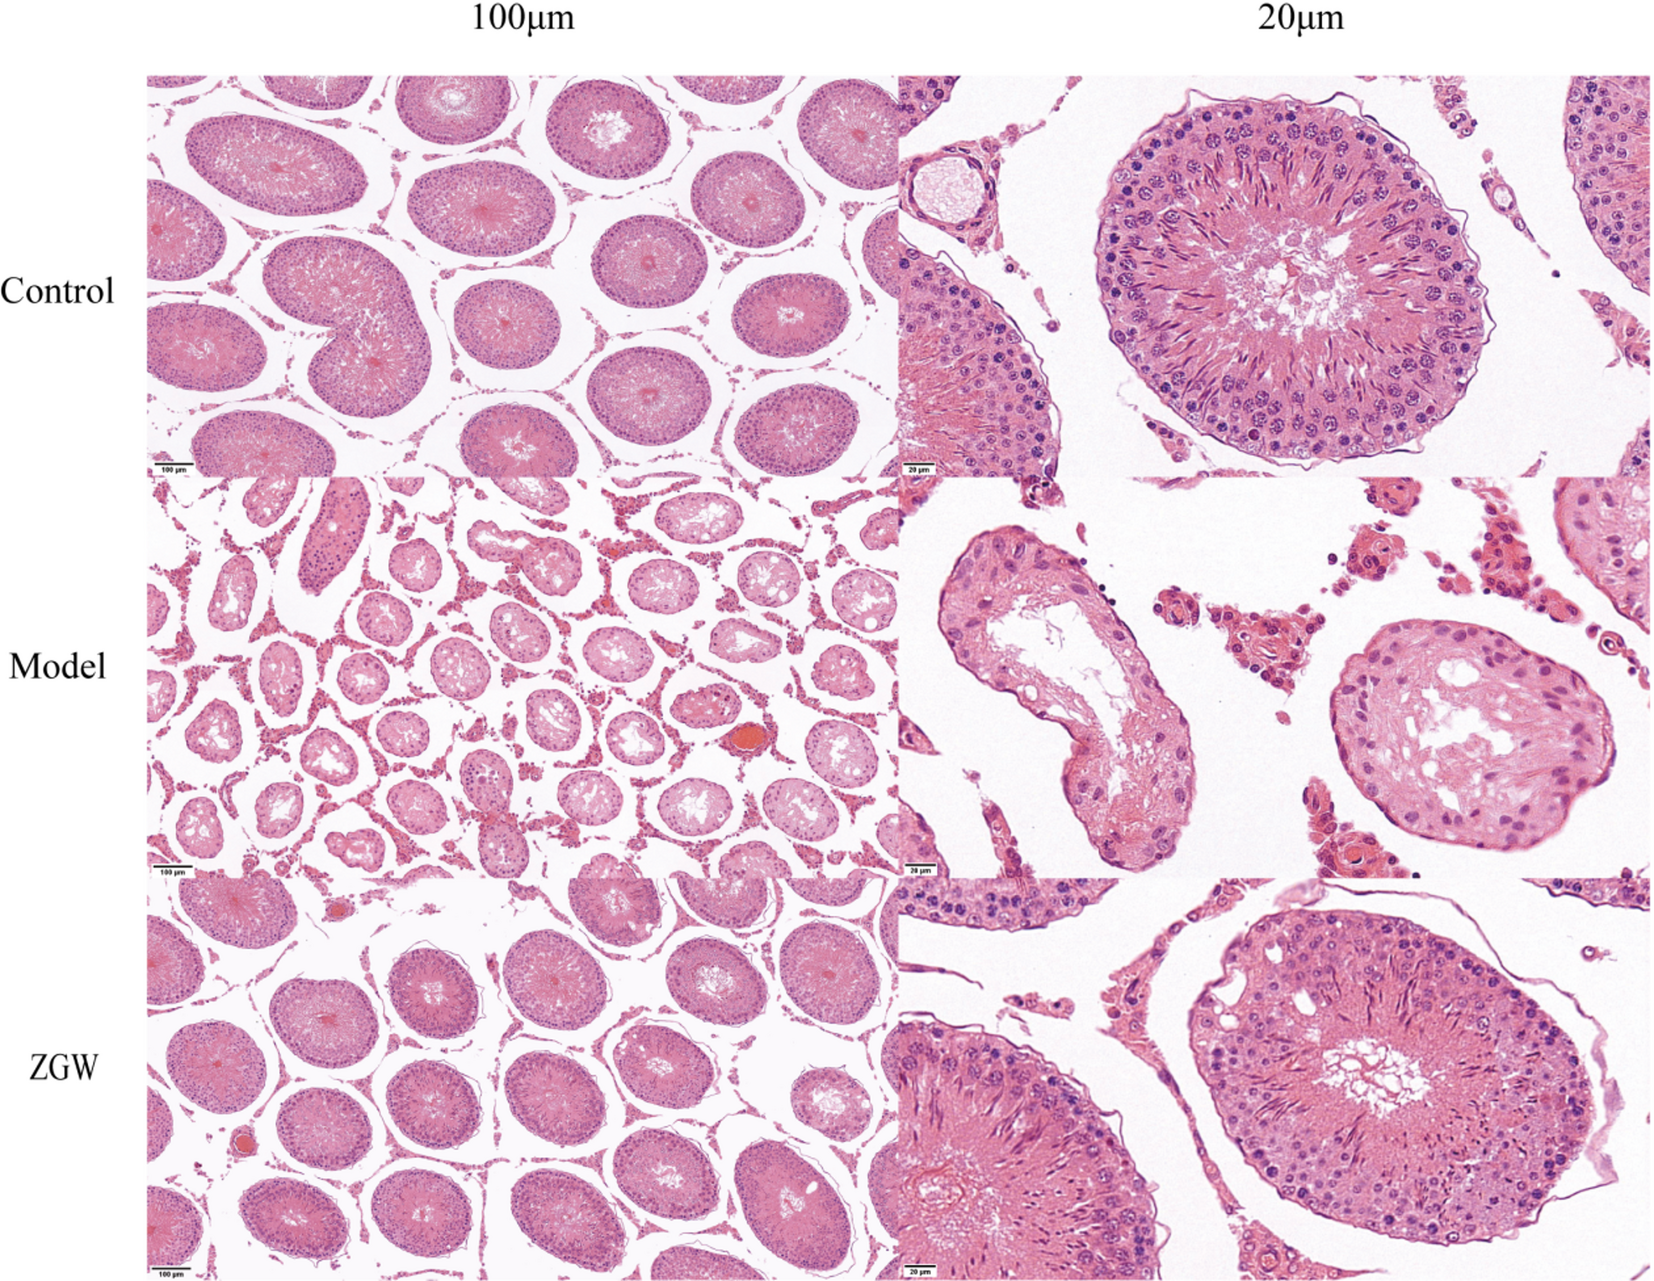

HE staining shows the protective effect of ZGW on rat testicular tissue.